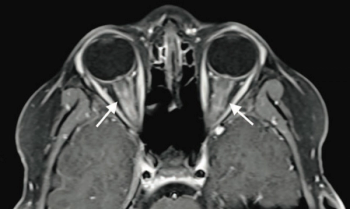

A 9-year-old boy with no significant medical history presented to the emergency department with 2 days of painless blurry vision. What's the diagnosis?